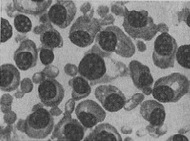

Патоморфологическим субстратом мієломної хвороби є ретикулярні плазматичні клітини кісткового мозку, лімфатичних вузлів, селезінки, печінки та ін. На гістологічних зрізах мієломних вузлів, як і в препаратах кісткового мозку, отриманих шляхом пункцій або трепанобиопсии кісток, виявляються характерні «миеломные клітини» - своєрідні, зазвичай великі плазматичні і ретикулярні клітини. Різноманіття морфологічних картин, властивих М. б., обумовлено різними стадіями розвитку і різним ступенем малігнізації (злоякісної трансформації) ретикулярних плазматичних клітин (рис. 1-6).

![]() Рис. 1. Стернальный пунктат при мієломної хвороби: плазмомиеломная метаплазія |